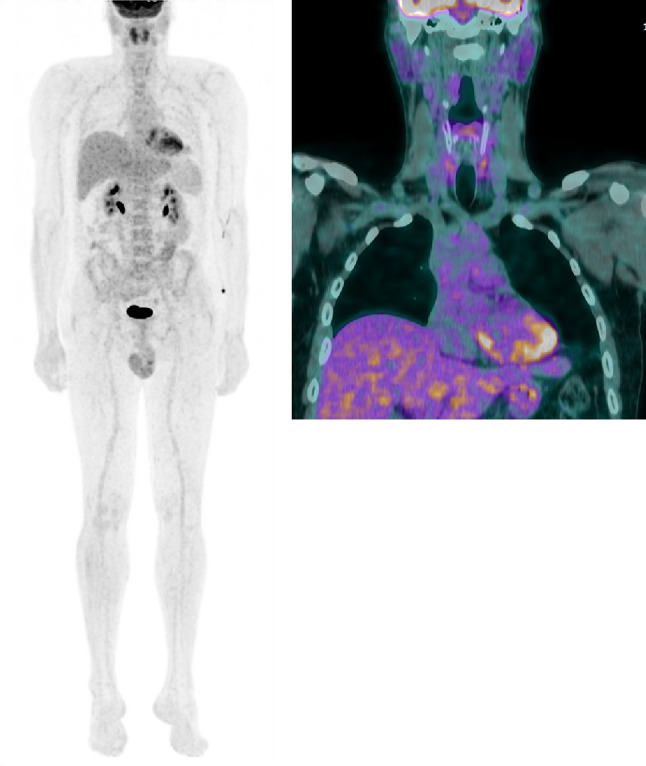

Given the morphologic, immunohistochemical, and molecular findings, a diagnosis of CEFTE was rendered. Substitution therapy with levothyroxine 125 mcg/day resulted in a satisfactory general condition. Neck US examination and 18FDG-PET/CT imaging, along with biochemical assessment, did not reveal any regional or distant persistence of disease at the 3- and 9-months follow-up visits (Fig. 7).

Fig. 7.

18F-FDG-PET/CT scan performed for post-surgical staging. Left panel: maximum intensity projection (MIP) showing no evidence of disease localisation in all body segments. Right panel: coronal view showing a faint, diffuse non-specific FDG uptake in the thyroid bed